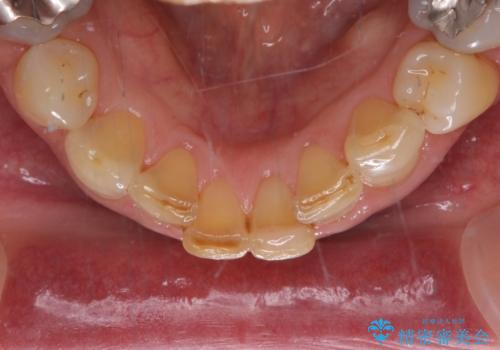

- 下顎前歯が痛んで近医を受診したところ、下顎前歯2本を抜歯してインプラント治療が必要と診断されたとのことで来院された患者様です。

診査の結果、下顎左側中切歯の神経が失活していることが痛みの原因であり、根管治療を行う必要があると診断されました。

根管治療を行った後にオールセラミッククラウンにて補綴することとしました。

隣在歯にも根尖部の炎症が及んでいるように見えましたが、術前診査では神経が失活している様子がなかったため、まずは原因歯から処置を行うこととしました。

初回の根管治療後には痛みが速やかに改善し、6か月後のレントゲン写真では根尖の病変が消失していることが確認できました。